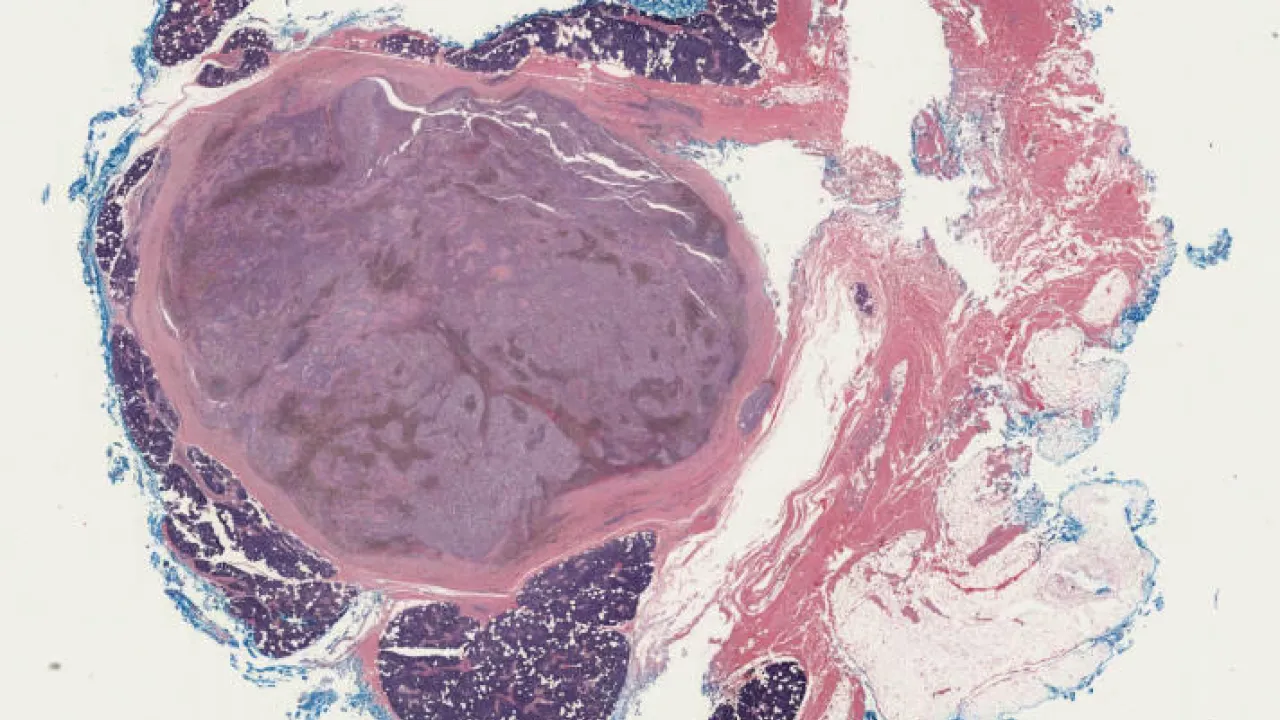

Scrotum, Idiopathic scrotal calcinosis